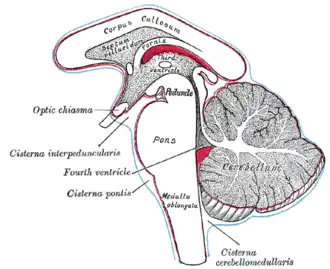

El puente de Varolio se ve en el centro Pons. | ||

El puente troncoencefálico, también llamado protuberancia anular o puente de Varolio (Pons, en latín), es la porción del tronco del encéfalo que se ubica entre la médula oblongada y el mesencéfalo.[1][2][3] Es el segmento más prominente del tronco del encéfalo, y su superficie anterior es convexa. Su nombre deriva del gran número de fibras transversales en la cara anterior que conectan los dos hemisferios cerebelosos.[4] Además de núcleos sensitivos y motores, contiene una porción de la formación reticular que participa en funciones importantes para la vida como el sentido de la vista, coordinación motora, el sueño y el estado de alerta.[4]

El puente se encuentra entre la médula oblongada y el mesencéfalo. El límite inferior se localiza en el surco bulbopontino formado entre el puente y la médula oblongada. Rostralmente, limita con el mesencéfalo por el límite inferior de la fosa interpeduncular que se forma por los pies de los pedúnculos cerebrales.[1] En la cara posterior está a su vez limitado por los pedúnculos cerebelosos superiores.[1] En el ser humano mide aproximadamente 3 centímetros de alto.[5]

La superficie posterior está oculta por el cerebelo con el que forma la parte superior del cuarto ventrículo.[1] Retirado el cerebelo se puede observar que forma la mitad superior del piso del cuarto ventrículo. En mitad se aprecia el surco medio y a ambos lados se encuentran dos elevaciones alargadas que reciben el nombre de eminencia media y colicuo facial en la parte inferior. Estas estructuras constituyen lateralmente el surco limitante y contienen núcleos motores como el facial o el abducens y sus fibras nerviosas.[4] En mitad de este espacio, denominado fosa romboidea, también se observa una apertura por el que se abre el acueducto y comunica el cuarto ventrículo con el tercer ventrículo en el mesencéfalo y forma parte del circuito para la circulación del líquido cefalorraquídeo.[1] Esta abertura en la superficie posterior del puente se denomina agujero de Luschka.[5]